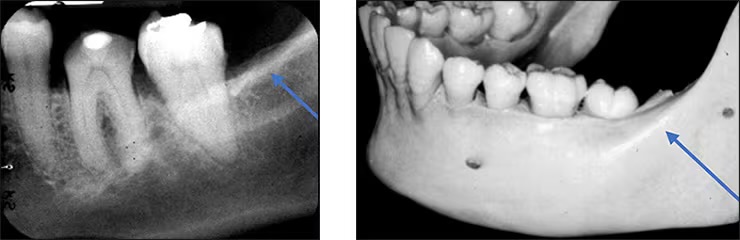

Submandibular gland fossa

Depression in the bone on the lingual aspect of the posterior mandible.

Bilateral below the maternal oblique ridge/mylohyoid line.

Is where the submandibular salivary gland rests.

Typically appears radiolucent